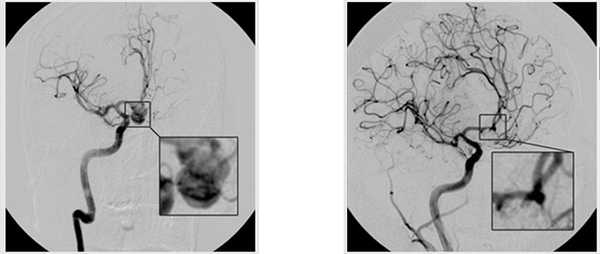

При эндоваскулярном вмешательстве доступ к аневризме осуществляется путем пункции бедренной артерии и ведения зонда под МРТ-контролем к месту операции. На конце зонда располагается баллон, вводимый в просвет аневризмы. После того, как баллон установлен и зафиксирован в аневризме, происходит эмболизация («закупорка») аневризмы, и она становится функционально неактивной.

эндоваскулярная эмболизация аневризмы

Все этапы операции осуществляются под строгим МРТ или КТ-контролем. После вмешательства пациент около пяти суток находится в отделении реанимации, после чего может быть переведен в отделение нейрохирургии.

После того как они подойдут к нужному месту при помощи слабых электрических импульсов выводятся спирали, которые расправляются внутри аномалии. Таким образом АГМ тромбируется и полностью исключается из кровяного русла, ее разрыв становится невозможным.

Не является редкостью, когда аневризмы имеют сложную структуру, широкое основание или форму веретена. Это может помешать стабильности установленных эмбол. В этом случае применяются баллоны и стенты.

Весь ход эндоваскулярной операции отслеживается врачами на цифровом ангиографе, в некоторых случаях для этой цели используют томографы (КТ или МР). В качестве контрастного вещества задействуют препараты, содержащие йод. Одним из неоспоримых преимуществ метода является применение местной анестезии, что важно для пожилых и ослабленных лиц, для которых невозможно осуществить клипирование, поскольку это представляет определенную угрозу для жизни.